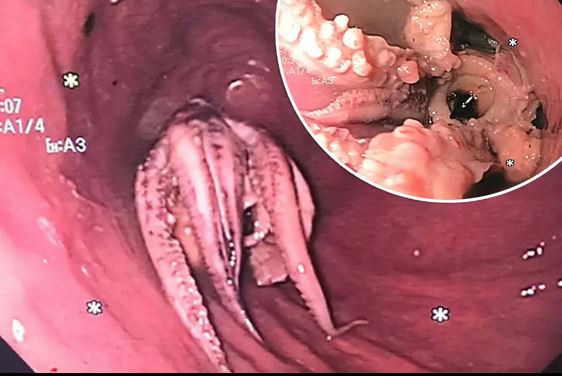

Οι γιατροί που τον εξέτασαν έμειναν άναυδοι όταν ανακάλυψαν ότι οι ενοχλήσεις στο λαιμό του άνδρα οφείλονταν σε ένα χταπόδι που είχε κολλήσει στο φάρυγγά του.

Οι γιατροί πραγματοποίησαν αξονική τομογραφία, η οποία αποκάλυψε μια υπερπυκνή μάζα στον οισοφάγο του άνδρα.

Μια επακόλουθη εξέταση έδειξε ένα χταπόδι ζωντανό με πλοκάμια να έχει σφηνωθεί δύο εκατοστά από τα όρια οισοφάγου-στομάχου. Οι γιατροί αφαίρεσαν το χταπόδι με λαβίδα.